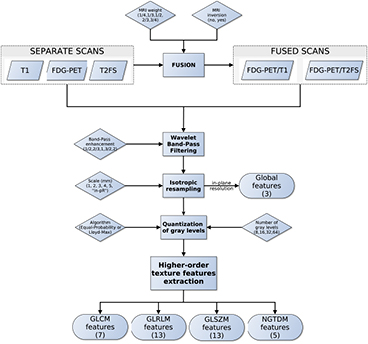

Considering the full set of texture extraction parameters of Global features and higher-order texture features (GLCM, GLRLM, GLSZM and NGTDM), a total of 27 405 and 182 700 scan-texture-parameter combinations were computed in this work for separate and fused scans, respectively. Figure 4 presents a summary of the workflow of extraction of texture features.

Figure 4. Workflow of extraction of texture features.